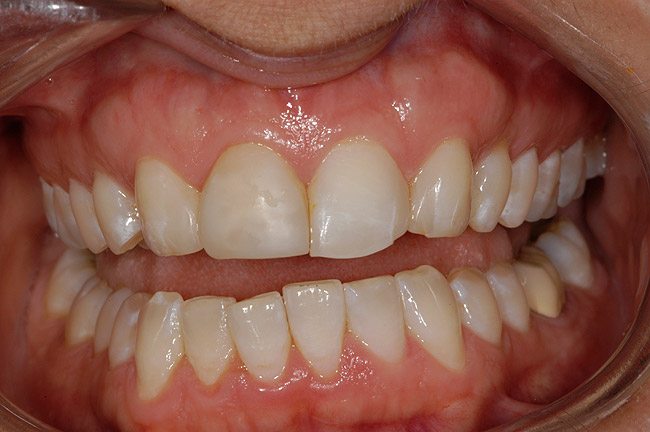

Figure 1 A patient presents after completion of orthodontic treatment for restorative enhancement of microdontic maxillary lateral incisors.

Figure 1